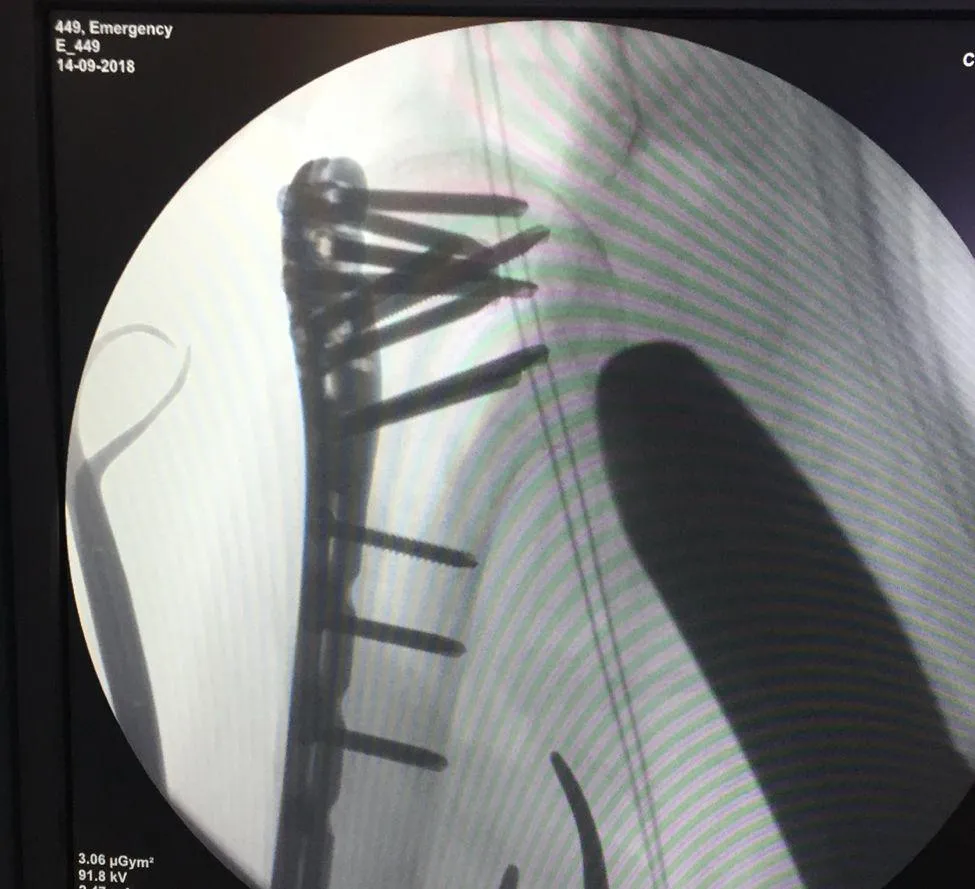

Paciente de 99 años

Fractura de cadera tratada con clavo TFNA

Paciente de 99 años con fractura de cadera. Se realizó fijación con clavo TFNA. Cada caso se evalúa de forma individual.